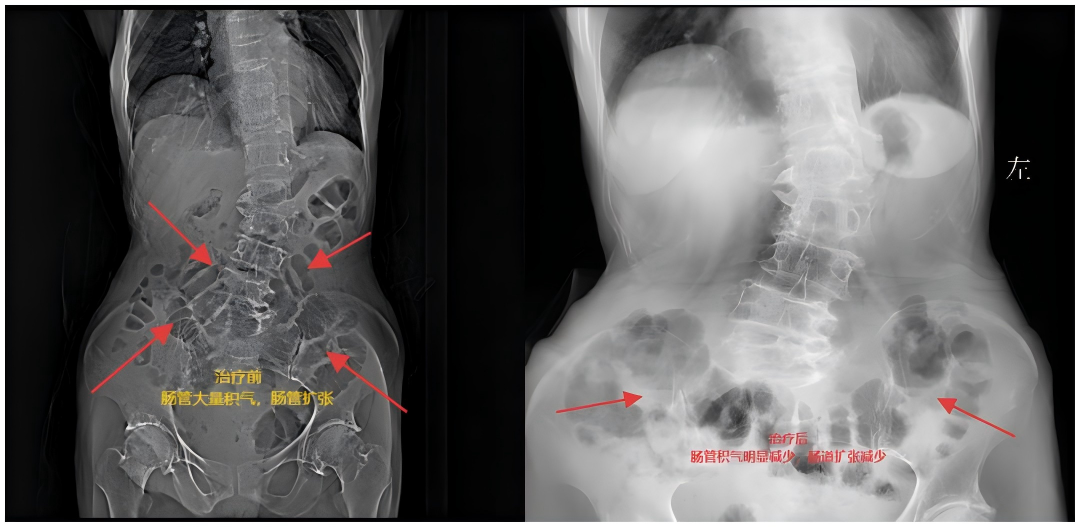

“放气了!” 治疗 24 小时后,黄奶奶终于出现肛门排气,腹胀明显减轻;48 小时后,腹痛基本缓解,可少量进食,复查腹部立位片显示 “肠管扩张消失,未见气液平”—— 梗阻完全解除!

治疗前后对比